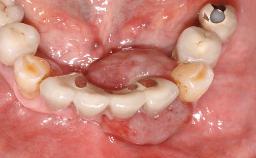

The fracture of an implant after it has been restored is one of the most severe complications. It most frequently occurs in partially edentulous jaws (1.5%). Most implant fractures involve implants with a diameter of 3.75 mm made of commercially pure titanium (Eckert 2010). Unfortunately, many cases are not reported or documented by the clinicians involved in resolving the problems created by the fracture. This case report describes the management of an implant fracture at site 36 in a middle-aged male patient. The implant had been restored with a screw-retained metal-ceramic crown.

Case Type Single-Tooth Space

Jaw Mandible

Area Posterior

Prosthesis Type FDP